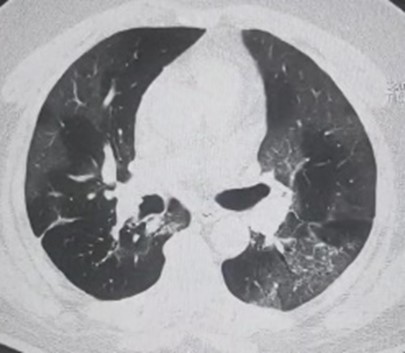

A sixty years old gentleman was brought to me with complains of breathlessness and low oxygen levels of 85%. He was admitted at other hospital for the treatment of COVID 19. Two days before he was discharged from that hospital after five days of treatment. He had history of heart disease and had undergone a procedure for the same. He responded to initial treatment but after a day of stabilization his condition deteriorated and I shifted him to ICU. His oxygen was falling rapidly and he was complaining of increasing uneasiness in breathing in spite of high flow of oxygen. I initiated support of noninvasive ventilation but oxygen level remained at 93%. He had spikes of fever and he became very sick. His oxygenation was becoming increasingly difficult and his heart rate and blood pressure were fluctuating. With ten days of rigorous monitoring and management, he showed improvement in his oxygen levels and blood pressure. He could be weaned from ventilator after almost twelve days. Another few days went uneventful but while he was stabilizing from this life threatening episode, on one morning he felt breathless again and his heart rate increased to 132 beats per minute. Now his breathing was deteriorating and oxygen was falling again. Increasing oxygen provision was not making any impact and he was again supported with BIPAP. His blood pressure decreased and he threw a new spike of fever. By then he was in ICU since twenty days. His lungs were significantly damaged and he was physically weak. There was a possibility of secondary infection in blood or lungs. At this stage secondary infections may prove fatal. Broad spectrum antibiotics to cover multi drug resistant organisms were considered. After almost five days of intensive treatment he showed improvement. I could wean him from ventilator. Now he was able to breath with moderate oxygen supply. He had no fever spikes. However his heart was beating fast. His 2D ECHO revealed mild reduction in pumping but nothing significant. He improved further and transferred to ward after few days. He kept improving in room and after forty days of hospital stay he was discharged. He is now recovering at home.

1_CT scan showing extensive disease

2_CT scan showing extensive disease